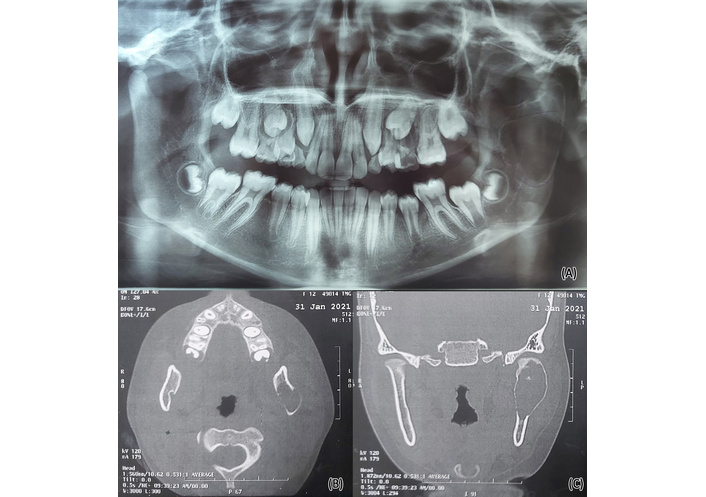

Preoperative radiographic analysis incorporated panoramic and chest X-rays. All selected patients had a computed tomography (CT) scan; the preoperative CT should have an interslice thickness of 1 mm, and the CT should not be older than 3 months (Figure 1). Data acquisition and processing: Patients underwent the preoperative cranialmaxillofacial and chest CT scans with 0.625 mm slice increment, 0.3 mm voxel size, 17 × 23 cm extended field of view, 1,120 kV, 5 mA, and “4 ms” exposure time with a stable molar occlusion [12], using ProPlan CMF software [FDA 510 (k) Number: K111641], Materialise Mimics 16.0 (Materialise, Leuven, Belgium) and DePuy Synthes (Johnson & Johnson, Solothurn, Switzerland), for virtual surgical planning.

Traumatic bone cyst of the left mandibular ramus and condyle. Panoramic X-ray film shows a left traumatic bone cyst related to the left ramus and condyle (A). Axial and coronal cuts CT shows a left traumatic bone cyst (B, C). Source from case No.3.